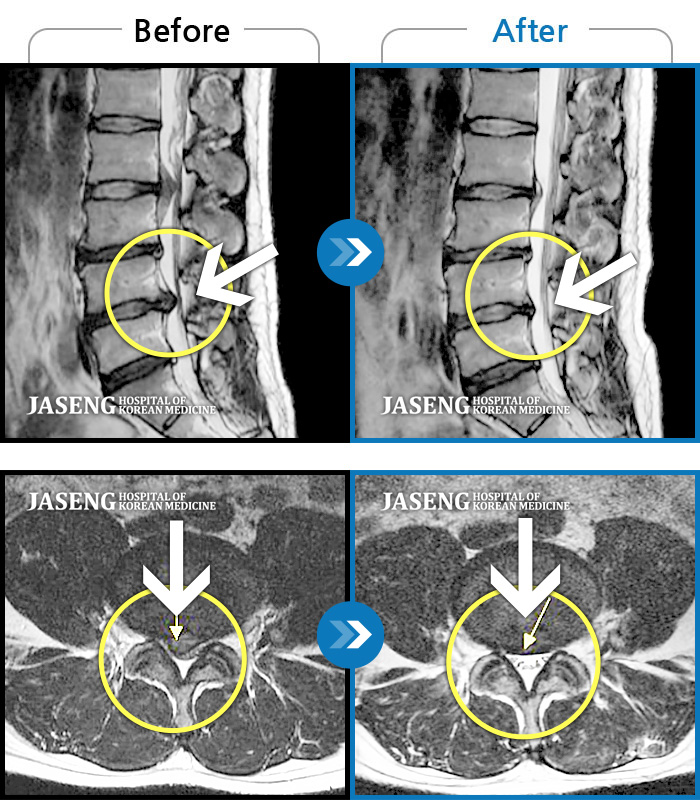

ȯںп Ǹ ǿ ԿǾ, ο ġ ۿ Ƿ ġḦ Ͻñ ٶϴ.